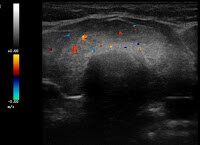

U.a. weisen Gewichtsveränderungen, Zyklusunregelmäßigkeiten und emotionale Instabilität auf Schilddrüsenfunktionsstörungen hin. Derbe Veränderungen in der Schilddrüse hingegen sind verdächtiger als weiche. Zu jeder Schilddrüsenuntersuchung gehört auch der Ultraschall von Schilddrüse und Halsweichteilen (Schilddrüsensonographie). Hierdurch lassen sich Größe und evtl. Veränderungen erkennen sowie relevante Strukturen in der vorderen Halsregion mit beurteilen, insbesondere Nebenschilddrüsen und Lymphknoten. Anhand des Schallmusters und des Durchblutungsmusters (Perfusion) lassen sich häufig bereits Krankheitsbilder festmachen.

So findet sich bei einer Autoimmunhyperthyreose (M. Basedow), einer zumeist schweren Form einer Schilddrüsenüberfunktion, eine ausgeprägte Echoarmut in Verbindung mit einer stark vermehrten Durchblutung des Schilddrüsengewebes. Von den Knoten verdienen solche mit Mikroverkalkungen und einer vermehrten Binnenperfusion verstärkte Aufmerksamkeit.